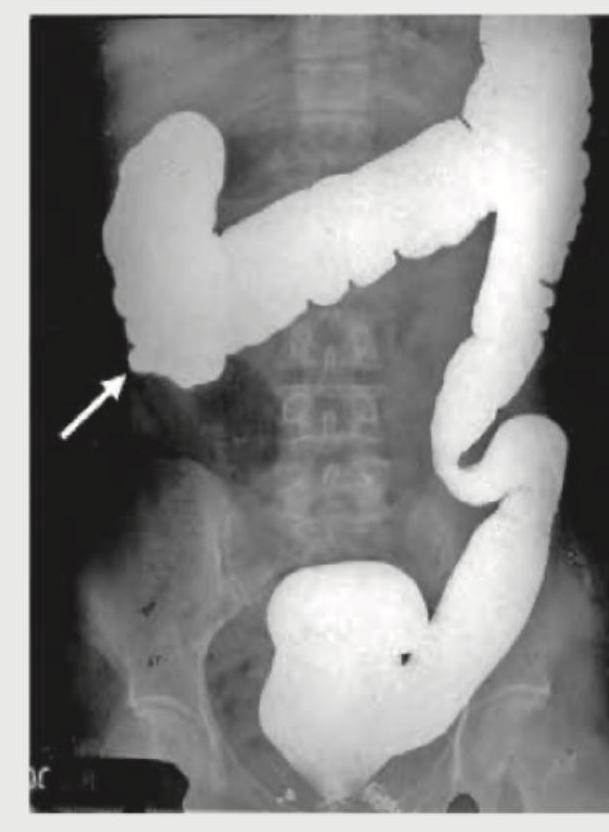

A patient presents with abdominal pain, diarrhea and weight loss. He gives a history of taking treatment for pulmonary TB. What does the barium film of the patient show?

Explanation: ***Pulled up cecum*** - The image shows a **deformed and pulled-up cecum** (indicated by the arrow) which is characteristic of **intestinal tuberculosis (TB)**, especially when combined with a history of pulmonary TB, abdominal pain, diarrhea, and weight loss. - This appearance is due to **fibrosis and contracture** caused by chronic inflammation from Mycobacterium tuberculosis infection affecting the ileocecal region, leading to architectural distortion and shortening. *Saw tooth* - A "sawtooth" appearance is typically associated with **spasm** or **haustral changes** in the colon, which is not the primary finding or most specific sign for intestinal tuberculosis. - While irregular contours can be seen, the dominant feature here is the **distortion and displacement** of the cecum, not simple serrations. *Intestinal perforation* - Intestinal perforation would result in the extravasation of contrast material into the peritoneal cavity, which is **not seen** in this barium study. - Perforation is an acute, life-threatening condition, and its imaging findings are distinct from the chronic changes shown here. *Diverticulum formation* - **Diverticula** appear as small, pouch-like outpouchings from the bowel wall, which are **absent** in this image. - Diverticulosis is a common condition but does not explain the patient's symptoms or the specific cecal deformity shown, especially in the context of prior TB.